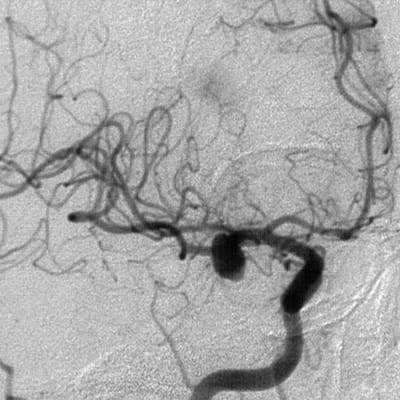

Если после проведения МРТ или КТ у врача остаются сомнения в диагнозе, если у данной аневризмы достаточно сложная форма либо очень небольшие размеры, большим подспорьем может стать дигитальная субтракционная ангиография (ДСА). Дигитальная - значит «цифровая». Субтракционная означает, что при исследовании исключаются изображения скелета, мягких тканей, видны только сосуды. Причём современная методика позволяет получать изображение в формате 2D (двухмерном) и 3D (трёхмерном) и даже вращать картинку, что даёт возможность уточнить локализацию аневризмы и оценить её расположение по отношению к магистральным сосудам головного мозга. Это помогает доктору понять, нужна ли операция в данном случае, и если да, то выбрать вид оперативного вмешательства и доступ к аневризме. Позже ДСА позволяет наблюдать за аневризмой (в том числе и после операции).

- Ангиографию. Церебральная ангиография позволяет установить расположение, форму и размеры аневризмы. В отличие от рентгенологической ангиографии магнитно-резонансная (МРА) не требует введения контрастных веществ и может проводиться даже в остром периоде разрыва аневризмы сосудов головного мозга. Она дает двухмерное изображение поперечного сечения сосудов или их объемное трехмерное изображение.

КТ-ангиография головного мозга (3D-реконструкция). Аневризматическое расширение левой средней мозговой артерии

· Церебральная ангиография является наиболее достоверным, инвазивным методом диагностики аневризм сосудов головного мозга. На церебральной ангиографии определяется локальное выпячивание стенки артерии головного мозга.